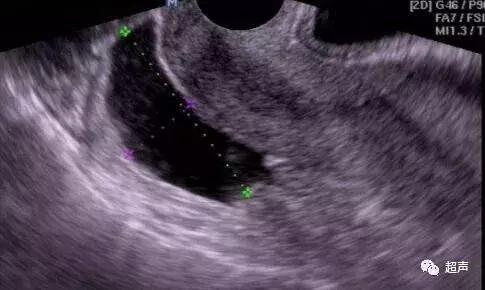

慢性盆腔炎表现为输卵管积水,炎性囊肿和肠腔与网膜粘连等混合性肿块图像,盆腔积液较多时可连成一片包围在子宫的周围,附件区可有囊性或混合性囊性肿块、穿刺液为淡红、微混、稀薄甚至脓液。炎性渗出积液表现于月经前后或月经中,或发生于流产术后引起腹痛。伴随子宫增大,子宫及附件回声减低,结构紊乱。尤以子宫旁结缔组织炎时积液量显著,可包围子宫, 使子宫漂浮其中似“吊床征”。抽液为淡黄色,性质为渗出液。